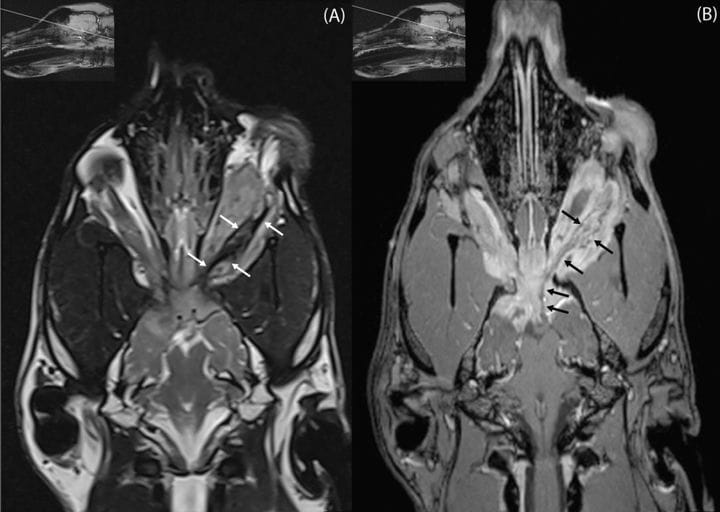

High-resolution images focused on the optic nerve with insets showing the exact imaging plane. (A) T2-weighted dorsal plane image optimized for the optic nerve. Small white arrows outline the retrobulbar portion of the mass encasing the optic nerve, which displays a focal, ill-defined hypointense thickening mid-aspect. (B) T1-weighted post-contrast dorsal plane image optimized for the optic nerve, acquired at a level just dorsal to (A). Small black arrows trace the enhancing retrobulbar portion of the optic nerve sheath complex extending towards the optic chiasm.

MRI revealed a large, lobulated, extra-axial mass extending from the retrobulbar space through the optic canals into the intracranial vault, compressing the optic chiasm and causing severe left-sided retrobulbar expansion. The mass was hyperintense on T2 and T2-FLAIR, showed mixed T1 signals, and demonstrated marked heterogeneous contrast enhancement with central necrosis, susceptibility artifacts, and meningeal enhancement. Biopsy demonstrated atypical spindle cell proliferation but was inconclusive. Necropsy identified a firm optic pathway mass (approximately 3 cm) effacing the optic nerve and infiltrating retrobulbar musculature and meninges. Histopathology revealed sheets of round neoplastic cells with perinuclear halos, microvascular proliferation, necrosis, and high mitotic activity. OLIG2 showed strong nuclear staining in 40–50% of tumor cells; GFAP was negative. Findings confirmed a high-grade oligodendroglioma originating within the optic chiasm and nerves. No metastases were observed.